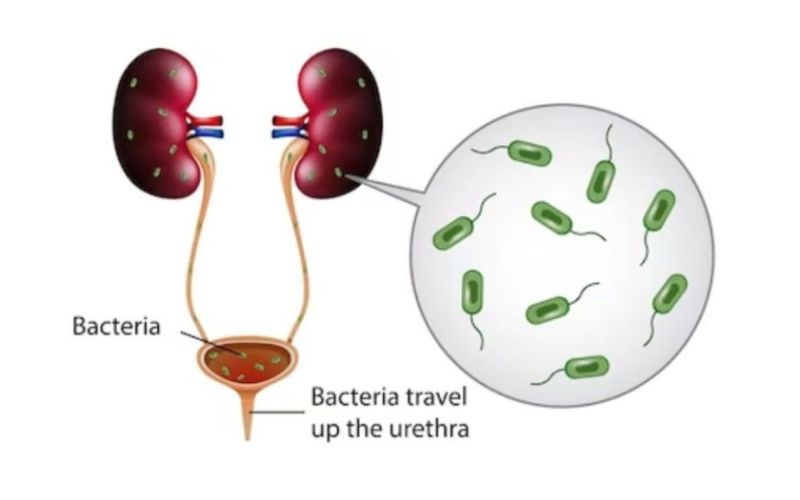

Urinary tract infections

Urinary Tract Infections (UTIs) are common infections affecting the urinary system, including the bladder, kidneys, ureters, and urethra. They occur when